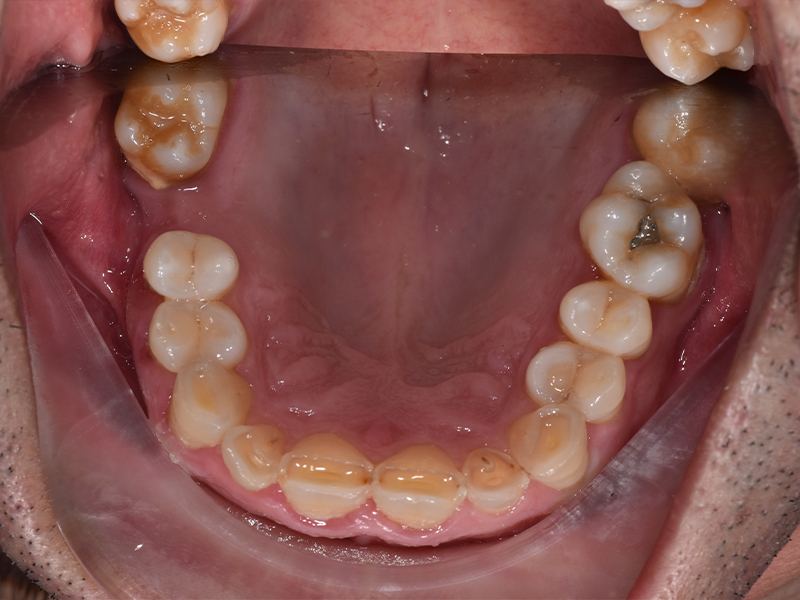

Salvatore, 48 anni, è arrivato nel nostro studio con una storia particolare: per oltre vent’anni aveva bevuto coca cola ogni giorno. Il risultato era evidente: denti fortemente consumati, molari mancanti, difficoltà a masticare e a sorridere. La moglie stessa, preoccupata per lui, ci ha chiesto di intervenire al più presto.

PRIMA